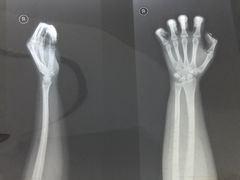

• 广州中医药大学第一附属医院(总院)

• -广州中医药大学第一附属医院(总院)